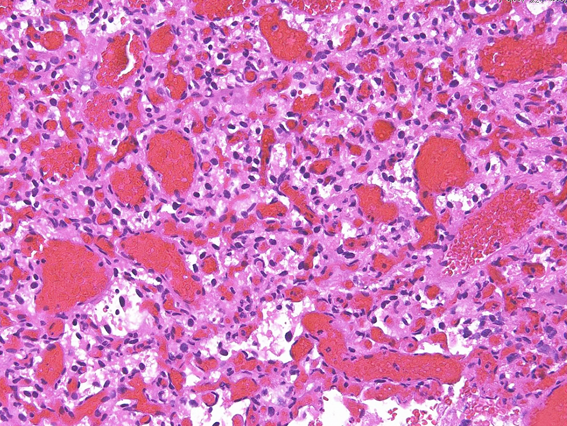

上記の症例の病理所見

弱拡では多数の血管が腫瘍の中に見られる,赤血球を含む大小の血管腔で構成される腫瘍である。

間質に増殖する淡桃色の胞体や空胞が豊かなstromal cells,この部分はcellular variantと呼ばれる。stromal cellでは,VEGF(血管内皮増殖因子)とVHL protein(フォンヒッペルリンドー病関連蛋白)が染まるので,この腫瘍細胞が激しい血管増殖を促していると考えられる。

毛細血管の増殖を主とするreticular variantと呼称される部分もある。大きな血管芽腫ではcellular variantとreticular variantが混在してあるのが通常である。